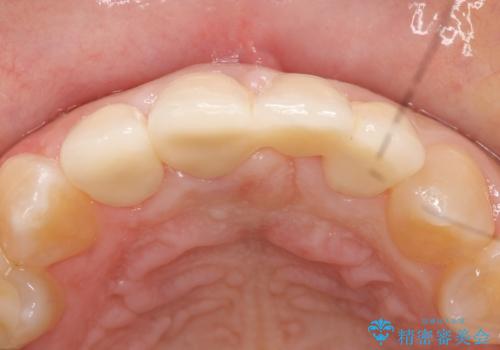

前歯4本をオールセラミッククラウンで補綴することで、歯の並びや色の改善を行いました。

今回用いたオールセラミッククラウンはジルコニアフレームという白い素材の上にセラミックを盛っているため、審美性が非常に高いのが特徴です。

また、ジルコニアは人工ダイヤモンドの材料にも使われているほど高い強度を持っており、そのためオールセラミッククラウンは審美性だけでなく、奥歯やブリッジの補綴も可能とするクラウンです。